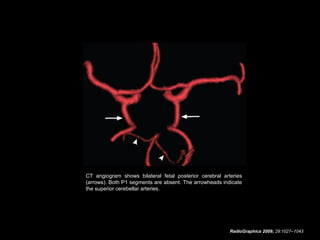

Bilateral fetal posterior cerebral arteries.

Three-dimensional multidetector CT angiogram shows bilateral

large posterior communicating arteries (arrows), which provide

most of the blood supply to the posterior cerebral artery territory.

Both P1 segments are present but hypoplastic.

CT angiogram shows bilateral fetal posterior cerebral arteries

(arrows). Both P1 segments are absent. The arrowheads indicate

the superior cerebellar arteries.

RadioGraphics 2009; 29:1027–1043

Bilateral fetal posteriorcerebral arteries. Three-dimensional multidetector CT angiogram shows bilateral large posterior communicating arteries (arrows), which provide most of the blood supply to the posterior cerebral artery territory. Both P1 segments are present but hypoplastic. RadioGraphics 2009; 29:1027–1043

CT angiogram showsbilateral fetal posterior cerebral arteries (arrows). Both P1 segments are absent. The arrowheads indicate the superior cerebellar arteries. RadioGraphics 2009; 29:1027–1043